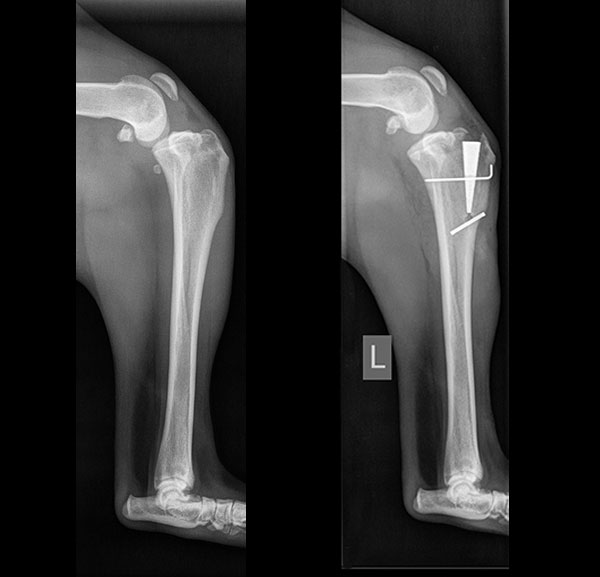

These before and after radiographs (X-rays) show alignment of the bones achieved with the MMP-TTA surgery at Blue Springs Animal Hospital.

The MMP TTA utilizes a titanium foam implant to advance the tibial crest and pull the head of the femur back into proper position. The titanium foam implant is porous and encourages bone growth into the implant.

In approximately 4-6 weeks bone fills in the implant enough to stabilize the repair. This bone stabilization of the foam implant shortens the period of exercise restriction required for healing after this procedure as compared to the TPLO procedure.